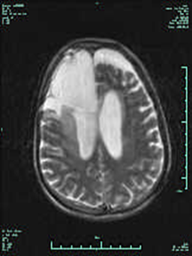

患者金某,61岁,6年前因患脑部胶质瘤在外院行手术治疗,术后恢复良好,生活过得也比较幸福。然而近半年来患者频发头痛,有时疼痛难忍,口服药物无法缓解,患者于2015年9月15日入住该院神经内科,经应用脱水、止痛等药物治疗症状无明显好转,查头颅MR示“颅内胶质瘤术后,水肿明显,中线略左移”,基本诊断脑部肿瘤复发。随着病程进展,脑疝一旦发生,随时有生命危险,家属陷入极度绝望之中。神经外科王风永主任医师得知情况后积极会诊,为缓解患者症状,延长生命周期,建议手术治疗,并组织科室进行讨论,考虑患者右侧额叶病灶越过中线结构并向左侧移位(10mm),大脑镰疝可能,周围脑水肿明显,中线左移,高颅压症状明显,具有明确手术指征,建议家属转神经外科行手术治疗。为了缓解患者症状,延长其生命时间,家属忧心忡忡地咨询王主任手术情况,王主任耐心、仔细、全面地把手术过程、手术并发症、术后康复及预后等情况告知家属,沟通比较充分,征得了家属的同意和支持。

术前MR

术后MR